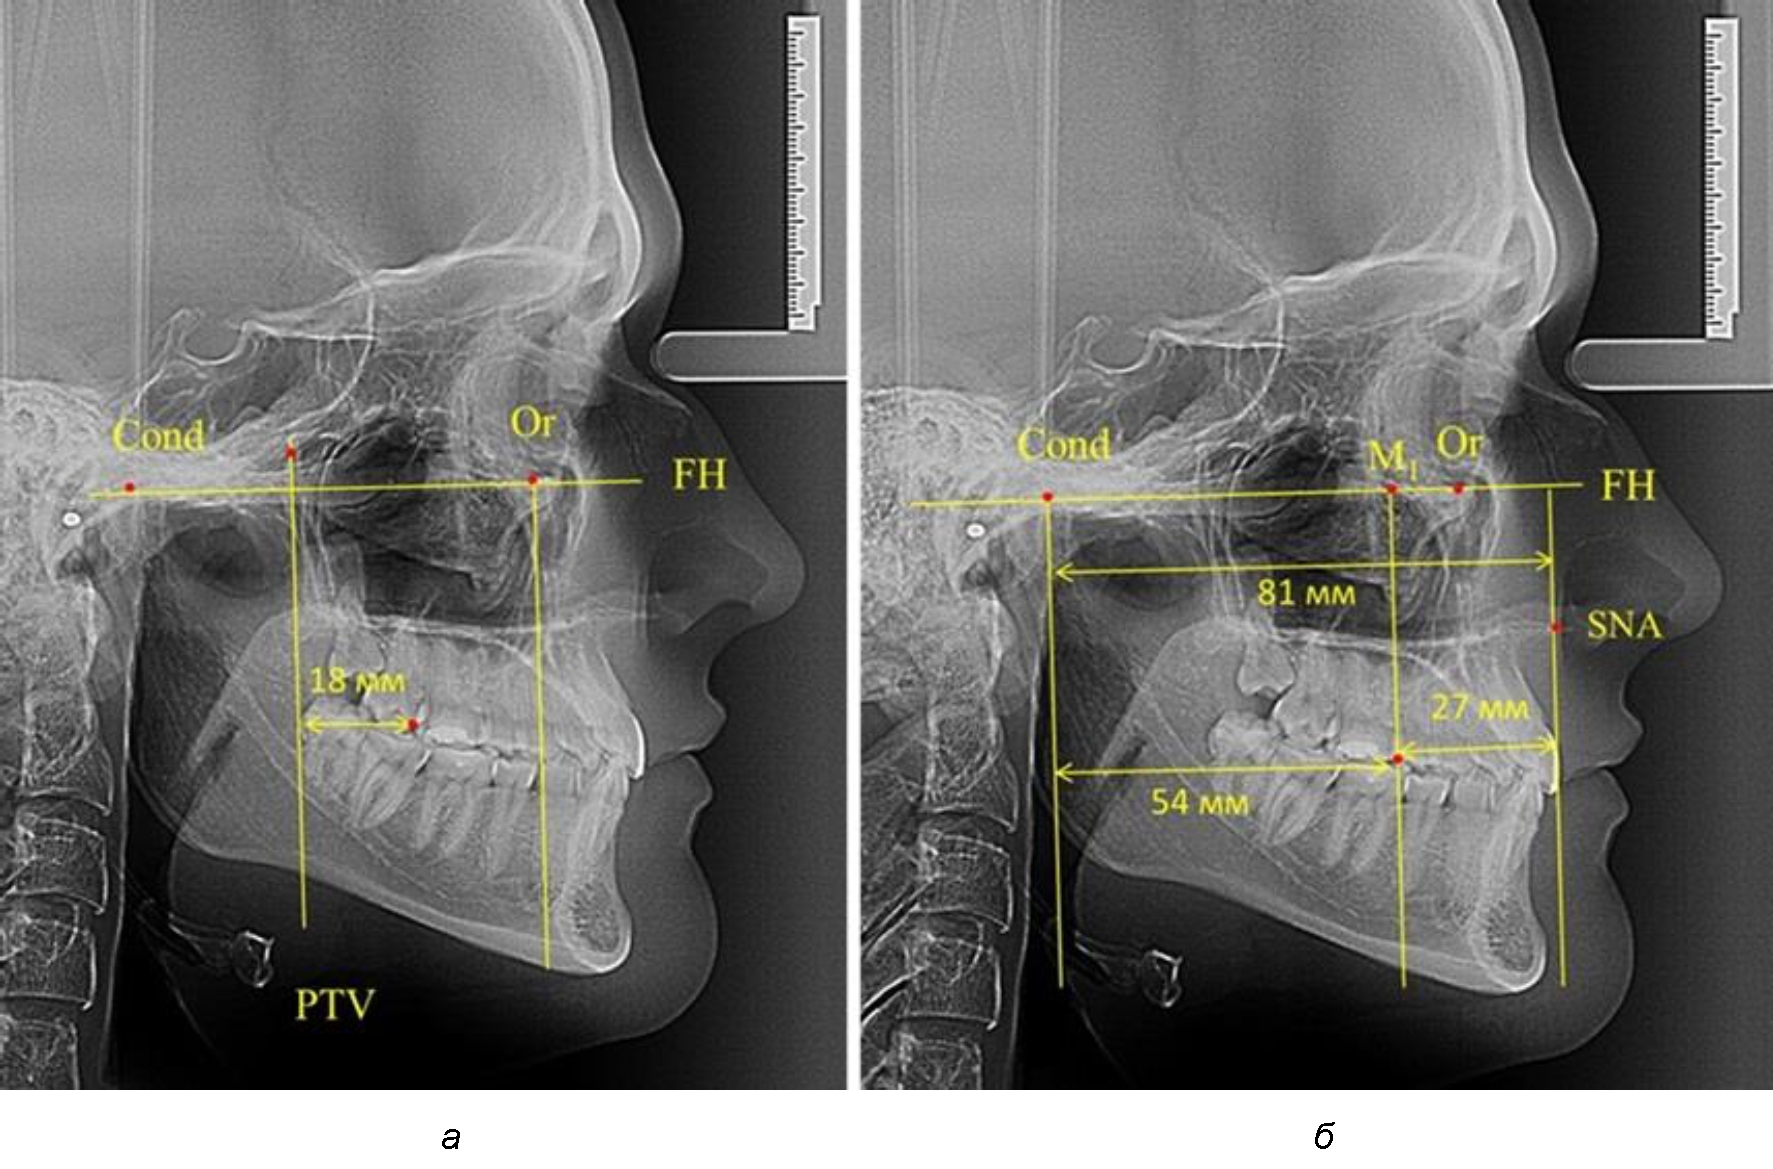

Рис. 2. Особенности положения первых моляров по R. E. McDonald (а) и по предложенному методу (б) при уменьшенном молярно-крыловидном расстоянии

Рис. 3. Особенности положения первых моляров по R. E. McDonald (а) и по предложенному методу (б) при увеличенном молярно-крыловидном расстоянии

Так, при расстоянии от крыловидной вертикальной плоскости PTV до дистальной поверхности верхнего первого постоянного моляра в 13 мм сагиттальный размер гнатического отдела был 82 мм. При этом отношение кондилярно-спинального расстояния к кондилярно-молярному размеру (54,5) было близким к коэффициенту 1,5, что представлено на рис. 2.

В то же время при увеличенном расстоянии от крыловидной вертикальной плоскости PTV до дистальной поверхности верхнего первого постоянного моляра, равное 23 мм, сагиттальный размер гнатического отдела составил 92 мм. При этом отношение кондилярно-спинального расстояния к кондилярно-молярному размеру (30,5), так же, как и при малых размерах, было близким к коэффициенту 1,5, что представлено на рис. 3.

Таким образом, наблюдалась эффективность использования относительных показателей при определении положения первых постоянных моляров. При этом наиболее целесообразно и с методологической точки зрения верным, было использование медиальной поверхности первого постоянного моляра. Построенная таким образом молярная линия отграничивала отдел зубной дуги с замещающими зубами от дистального отдела с добавочными зубами постоянного прикуса, в частности, постоянных моляров.